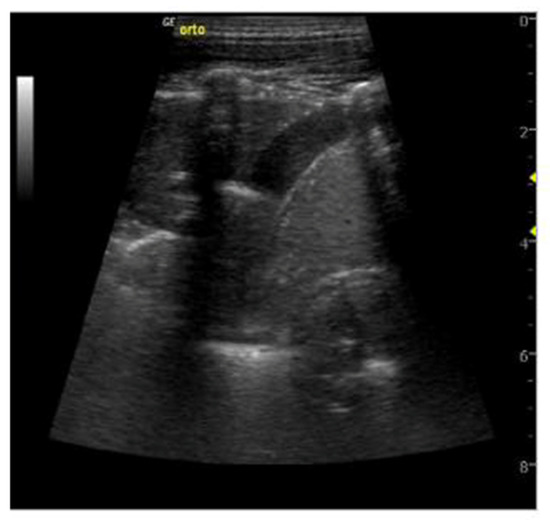

- Ruby, L.C.; Kadavigere, R.; Sheshadri, S.; Saravu, K.; Bélard, S. Pulmonary aspergilloma on transthoracic ultrasound. Infection 2021, 49, 1337–1340. [Google Scholar] [CrossRef]

- Rea, G.; Sperandeo, M.; Lieto, R.; Bocchino, M.; Quarato, C.M.I.; Feragalli, B.; Valente, T.; Scioscia, G.; Giuffreda, E.; Foschino Barbaro, M.P.; et al. Chest Imaging in the Diagnosis and Management of Pulmonary Tuberculosis: The Complementary Role of Thoracic Ultrasound. Front. Med. 2021, 8, 753821. [Google Scholar] [CrossRef]

- Giannelli, F.; Cozzi, D.; Cavigli, E.; Campolmi, I.; Rinaldi, F.; Giachè, S.; Rogasi, P.G.; Miele, V.; Bartolucci, M. Lung ultrasound (LUS) in pulmonary tuberculosis: Correlation with chest CT and X-ray findings. J. Ultrasound 2022, 25, 625–634. [Google Scholar] [CrossRef]